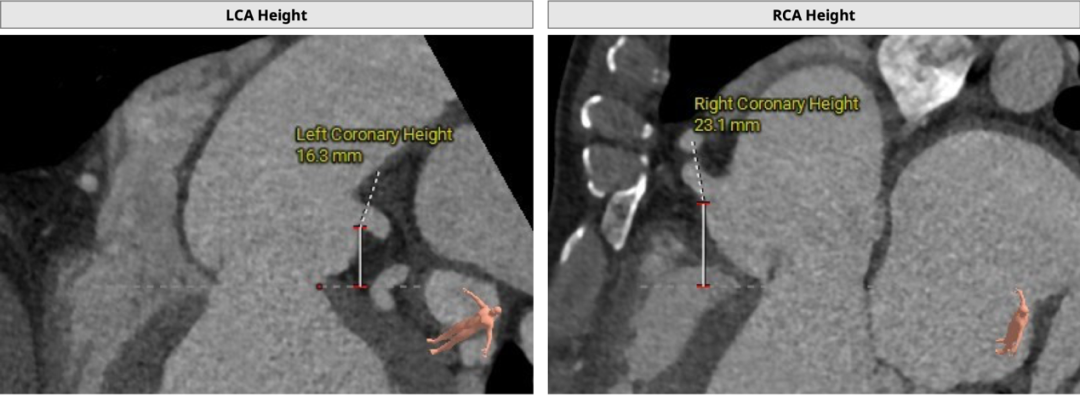

71岁男性,主动脉瓣轻度狭窄重度反流。三叶瓣,左右交界有钙化,瓣环均径29mm,LVOT均径28.9mm,瓣上6/8mm预计展开均径分别是26.6mm/27.2mm,左冠高度19mm,右冠高度25mm,STJ均径31mm,升主均径35mm患者室壁较厚,高度26mm,窦宽38/37/39mm,升主均径约34.1mm,左室壁较厚,心尖部室壁厚约4mm。此外,右侧入路较窄处内径约7.5mm,右侧髂外、主动脉弓见少许钙化强回声,腹主动脉部分节段走行稍扭曲。心尖部室壁较薄,主动脉根部解剖结构偏极限,对临床团队术前评估及术者术中精准释放有很高要求。

该患者为大瓣环反流,左右交界有钙化,拟植入Vita Flow® 30瓣膜,瓣下2mm释放。